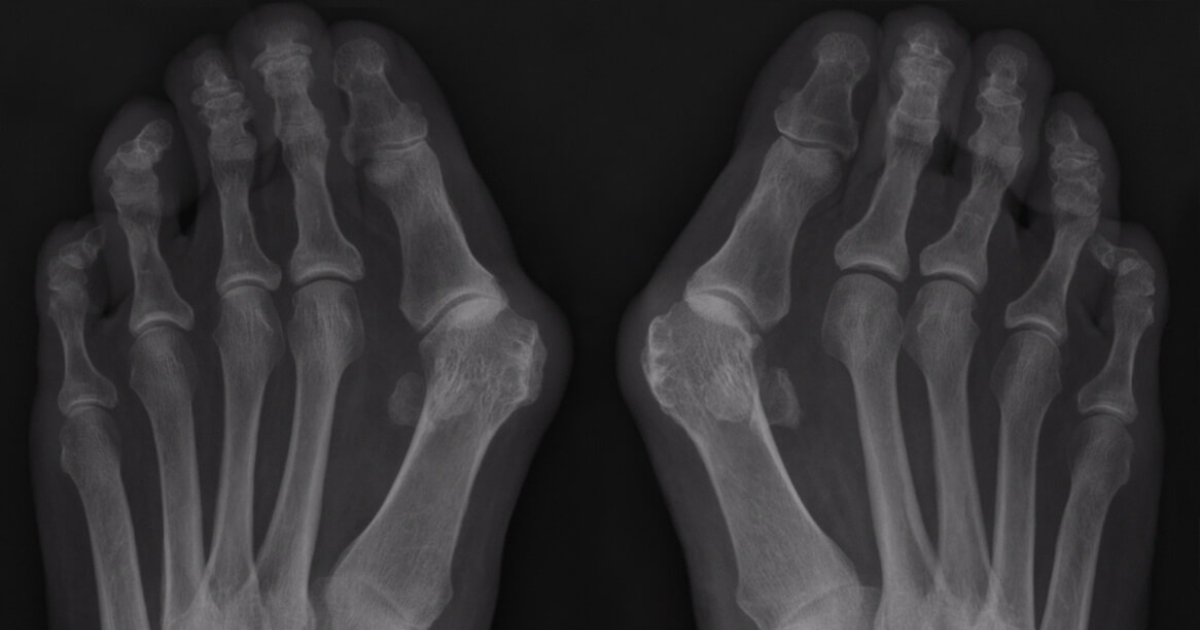

, door Thomas De Vriendt Hallux Valgus: oorzaken, feiten en een 3-stappenplan

Hallux valgus, ook wel een grote teen afwijking genoemd, is een veelvoorkomende voetaandoening. Ontdek de oorzaken, symptomen en effectieve behandelmethoden, inclusief hoe barefoot schoenen kunnen...